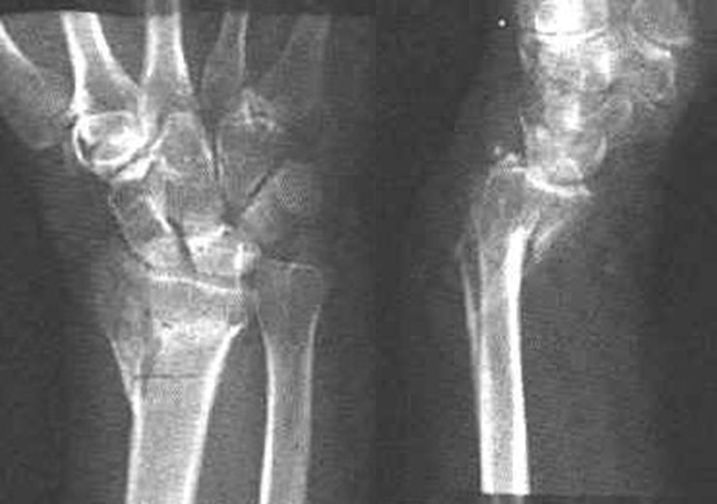

月骨周围脱位